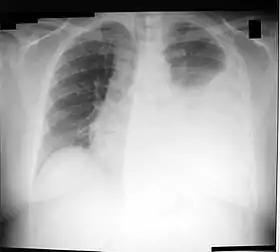

![]() تصوير الصدر بالأشعة السينية showing a left-sided انصباب جنبي (right side of image). This can be treated with thoracentesis. | |